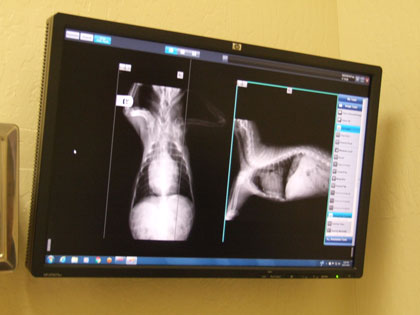

ちびの早い呼吸には三つの原因が考えられる...

◎心臓病の悪化

これはレントゲンでクリアしましたよ

弁膜症が治った訳ではありませんが

心臓肥大だったのに普通に戻って 従って気管支も障害物無し!

肺にも水が溜まっていなかったのです!

5年間 投薬しているDiuretics(利尿薬) ACE Inhibitors(抗高血圧薬)の効果が出ているのですね

上野先生もこれには驚いておられました

この犬は凄いね~と言われましたよ